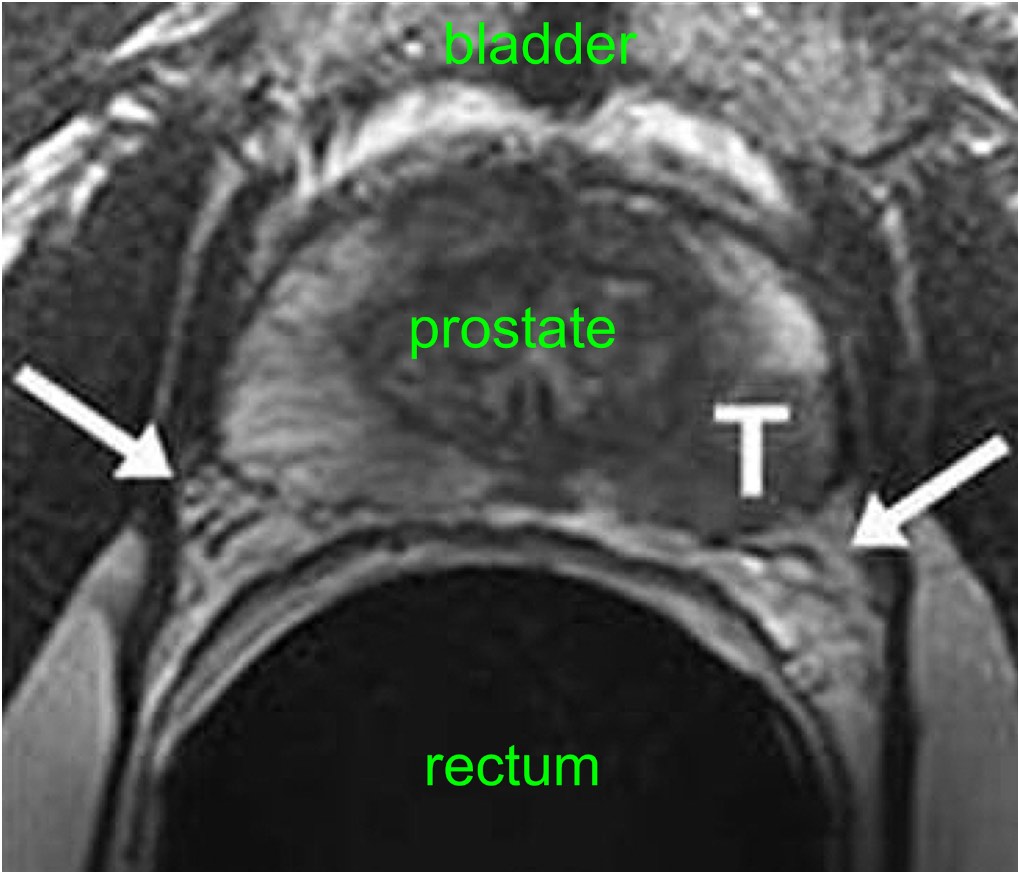

MRI to Diagnose Prostate Cancer – https://debuglies.com

MRI scan of prostate cancer – Santis | Private London prostate cancer …

[PDF] Local staging of prostate cancer with MRI. | Semantic Scholar

Prostate cancer, MRI scan – Stock Image – M865/0208 – Science Photo Library

Typical images show prostate cancer invading rectum. a. Pelvic MRI …

Extracapsular extension of prostate cancer on various sequences. (A …

Coloured MRI scan showing prostate cancer – Stock Image – M865/0142 …

The Radiology Assistant : Prostate Cancer – PI-RADS v2

Prostate Cancer Radiology : Multiparametric Mri For Prostate Cancer …

75 best images about MRI Technology on Pinterest

MRI: My Radiology Insight

The Radiology Assistant : Prostate Cancer – PI-RADS v2